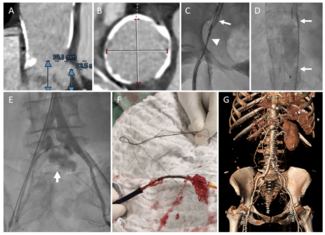

A 76-year-old female with severe symptomatic aortic stenosis underwent cardiac CT angiography imaging. Severe calcification of the ascending aorta (porcelain aorta) precluded surgical aortic valve replacement.